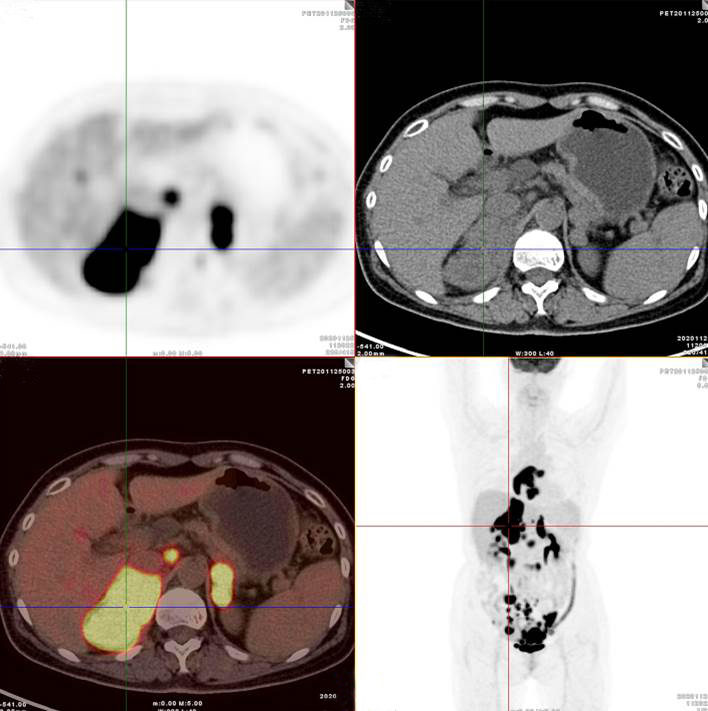

雙側(cè)腎上腺病灶、腹膜后淋巴結(jié)放射性攝取明顯增高

膽囊及雙腎上腺病灶、腹膜后淋巴結(jié)放射性攝取明顯增高